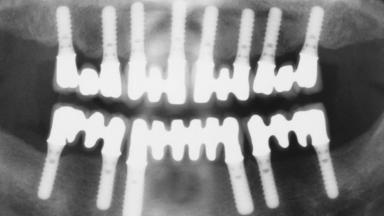

Immediate Loading of Eight Implants in the Maxilla and Six Implants in the Mandible and Final Restoration with Three-Unit and Four-Unit FDPs

# of Implants 14

Type of Implants One-Piece

Defining Characteristics Fully edentulous upper jaw to be rehabilitated with four or more implants

Modality 6+ implants with immediate loading

Defining Characteristics Fully edentulous upper jaw to be rehabilitated with an implant-borne fixed dental prosthesis

Loading Protocol Immediate